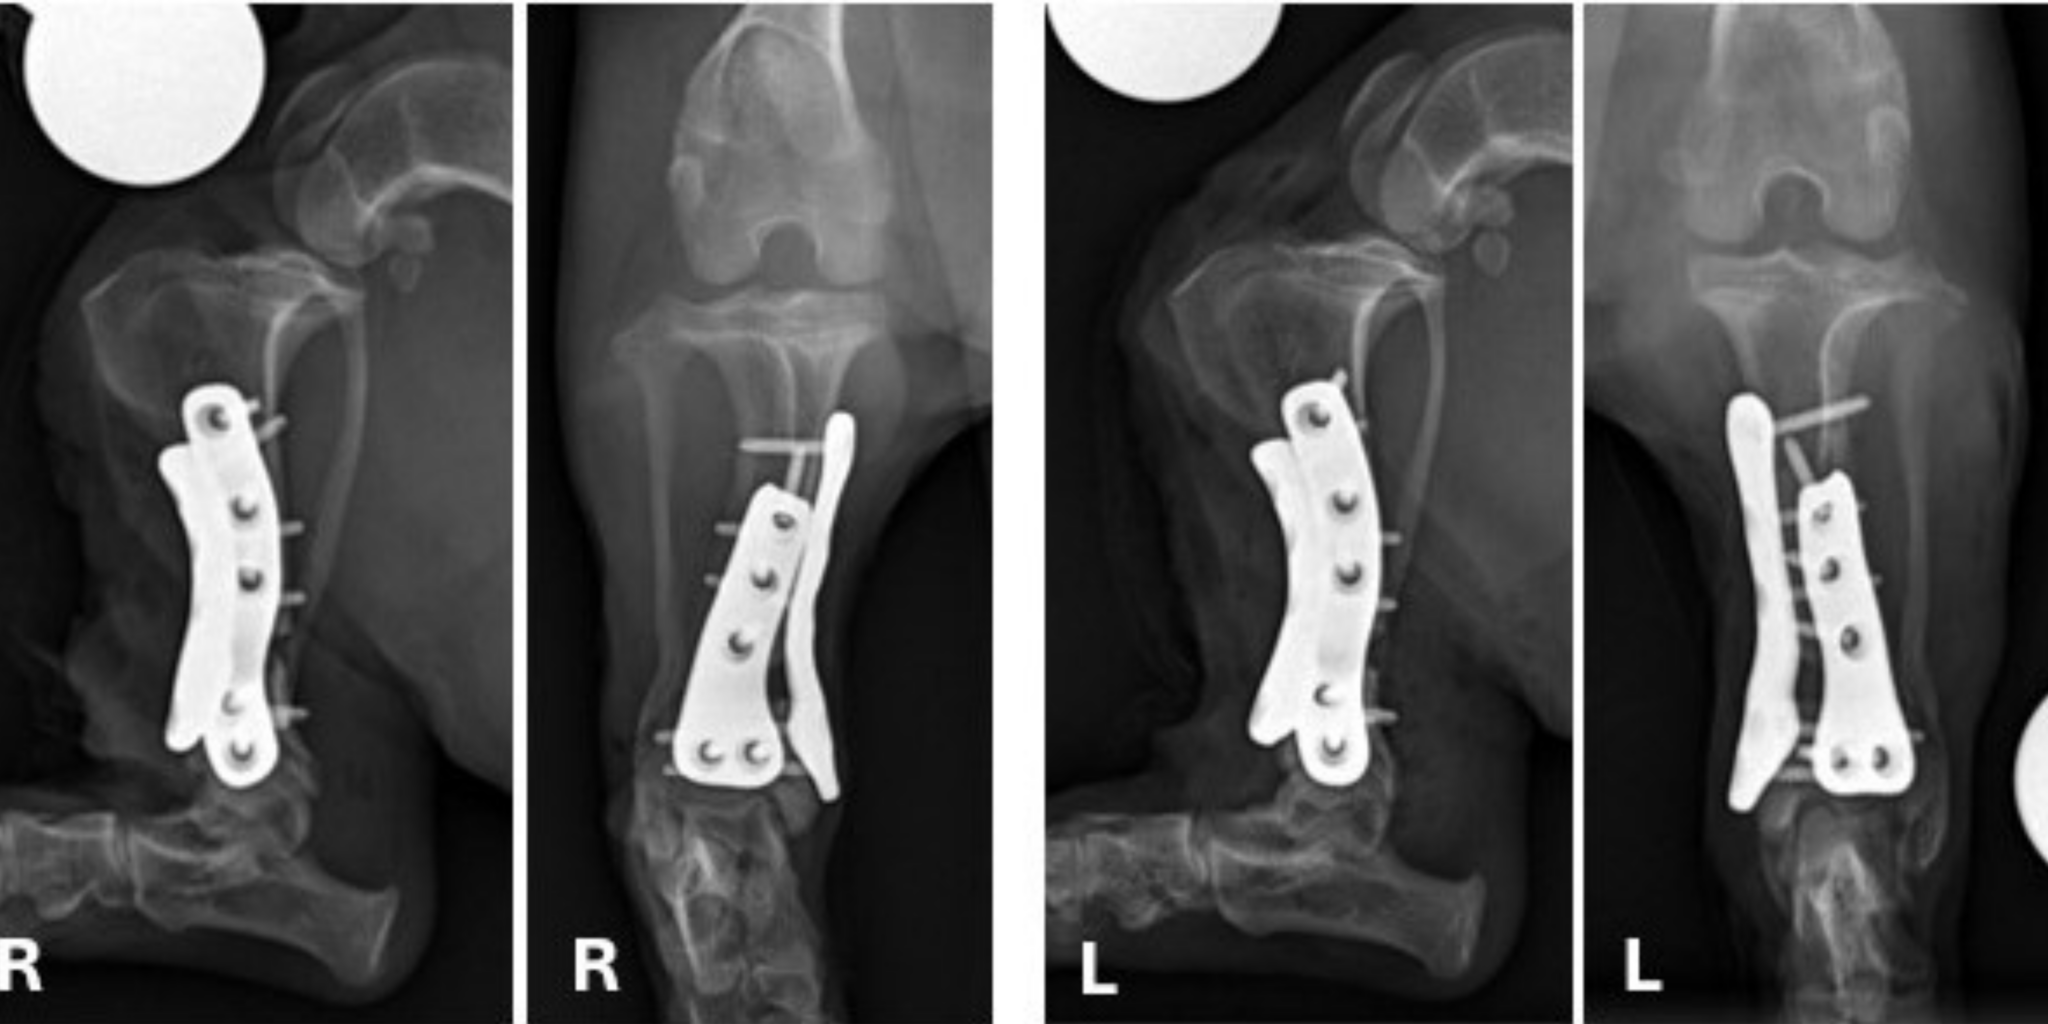

They agreed Chunk needed surgery to correct the deformity, so Bleedorn worked with Dr. Bill Oxley of Vet3D, a 3D consulting company in the United Kingdom, to create custom 3D-printed surgical guides and titanium plates.

“You can import the CT into the computer-aided design (CAD) software, so you can look at the bones and their alignment on the computer,” Bleedorn said. “Then we can actually do a virtual correction rehearsal surgery all on the computer where I cut the bones and manipulate them, so I know precisely what my target plan will be. Once I’m happy with the plan, then I will build a guide that ensures I can make the cuts in the right spot in surgery.”

It sounds futuristic, but the technology has been in use for about 20 years in veterinary medicine. “The guide is printed, sterilized, and then physically placed on the tibia and secured with pins onto the bone and we basically cut on the guides like a 3D template,” Bleedorn said. “Custom metal printed plates are a more recent addition to this approach but allow tremendous opportunity for improvements in challenging cases such as Chunk.”

In May, Bleedorn, CSU orthopedic surgeon Dr. Joey Sapora, and resident Dr. Zach Wund performed the procedure. They cut and fixed the bones with custom 3D-printed guides and two tiny titanium plates in each leg. “The repair is very strong because the plates fit perfectly on Chunk’s tibiae,” Bleedorn said.

He bounced back remarkably well, and six weeks later, his bones were healed with no signs of infection.